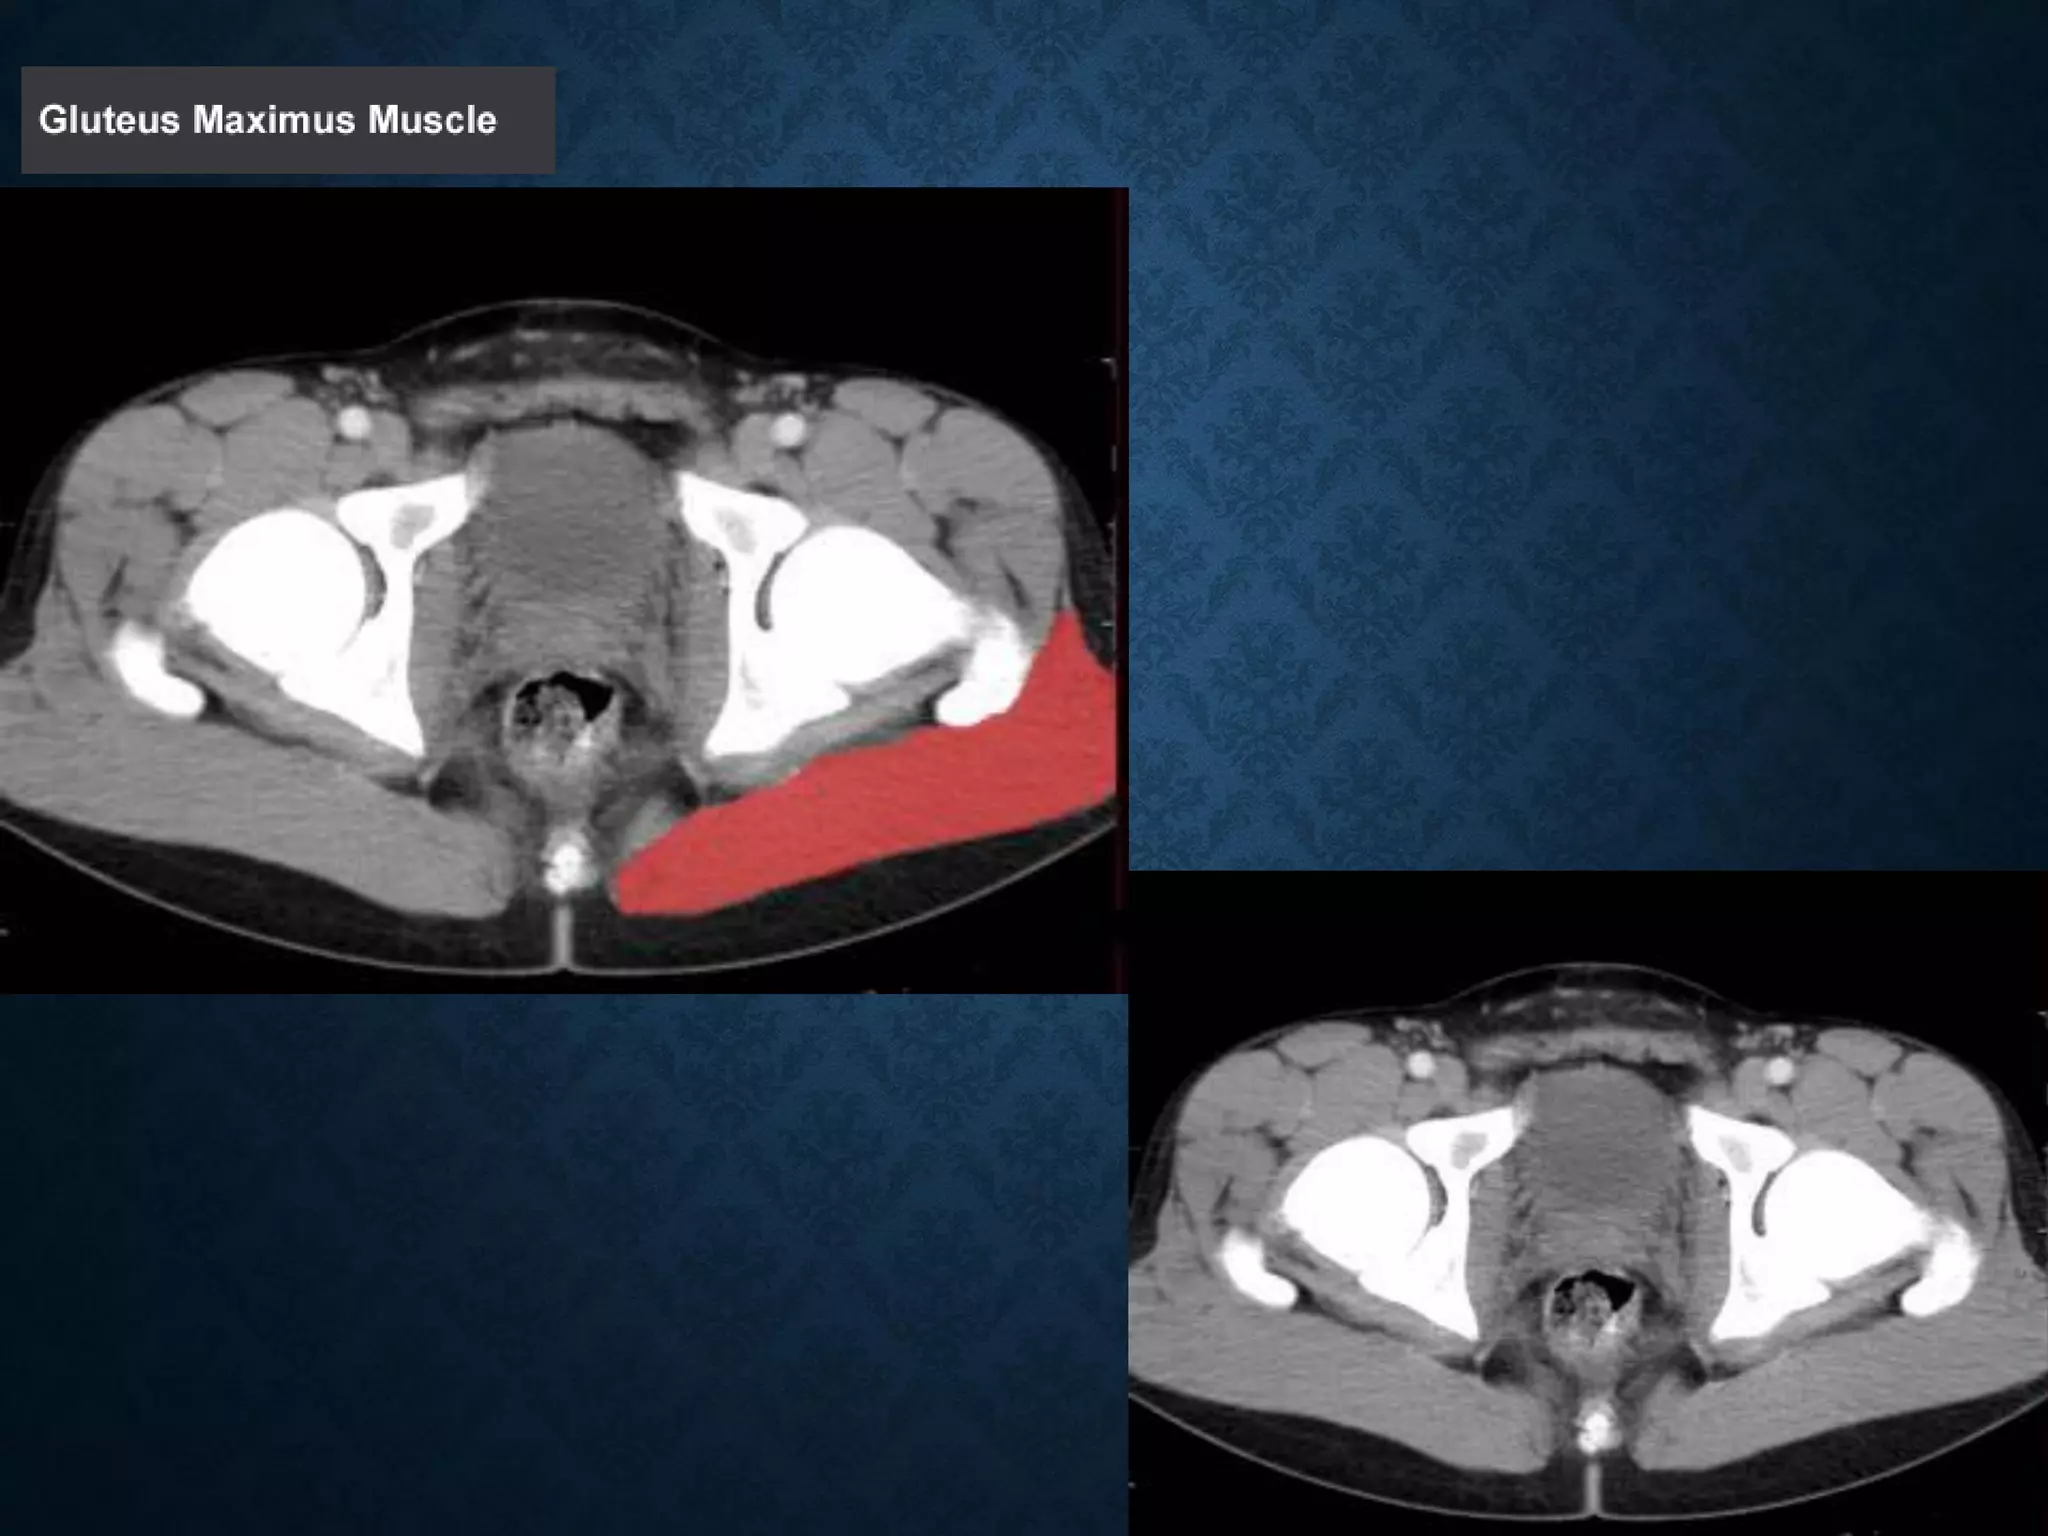

Normal Anatomy- Section 12

Normal Anatomy- Section 13

Normal Anatomy- Section 14 (female)